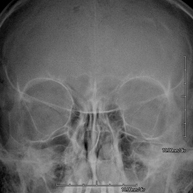

- RX Cráneo

Técnica mediante la cual, utilizando rayos X, se obtienen imágenes del cráneo para su estudio. Indicaciones: traumatismo, cierre precoz de suturas craneales. - RX Senos Paranasales

Técnica mediante la cual, utilizando rayos X, se obtienen imágenes de las órbitas para su estudio. Indicaciones: cuerpo extraño ocular, traumatismo, infecciones. - RX Mandibular